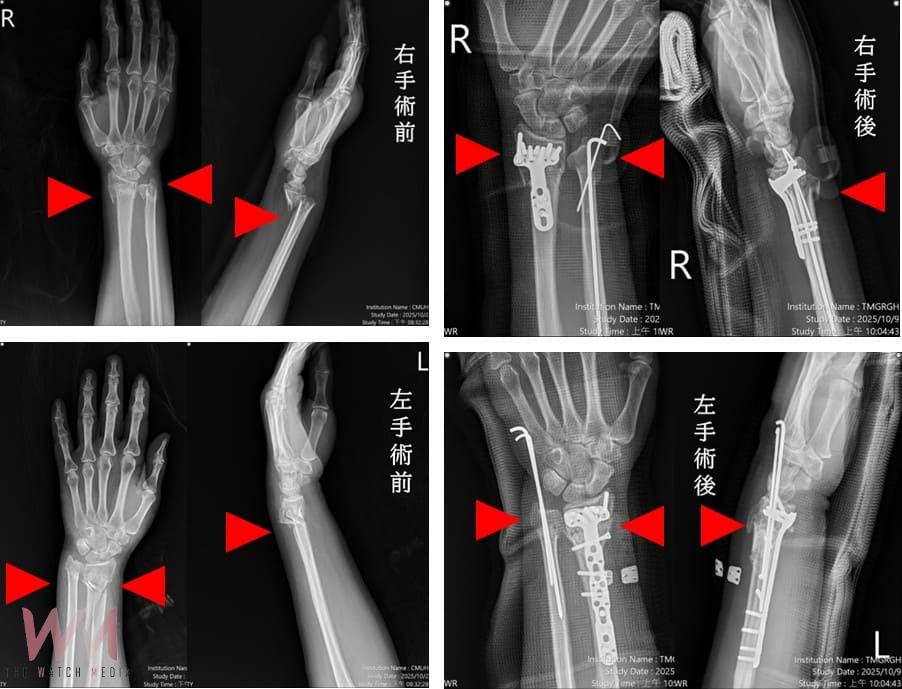

(觀傳媒中彰投新聞)【記者廖妙茜/台中報導】臺中市立老人復健綜合醫院創醫療新紀錄!一名57歲婦人因交通事故導致雙手多處骨折與脫位,經本院急診救治,診斷為粉碎性複雜性骨折,本院啟動「多主治醫師協同手術機制」,由骨科部蘇伯翰、江晟弘、毛睿廷三位主治醫師同步進行左右手微創手術,僅一小時即完成四處骨折修復,術後三日順利出院。此創新機制將傳統五小時的手術時間縮短為一小時,大幅減少疼痛與麻醉副作用,並降低醫療人力負擔。

蘇伯翰醫師指出,該名傷患送至本院急診後,即時進行復位與石膏固定,並於24小時內安排開刀,採用「多主治協同手術模式」,由三位主治醫師同時操作左右手四處骨折微創手術,縮短手術時間至約一小時,協同分工可加快病患恢復速度,並提升安全性。患者傷口小、出血少,隔天即可開始復健,三天後平安出院,恢復良好。